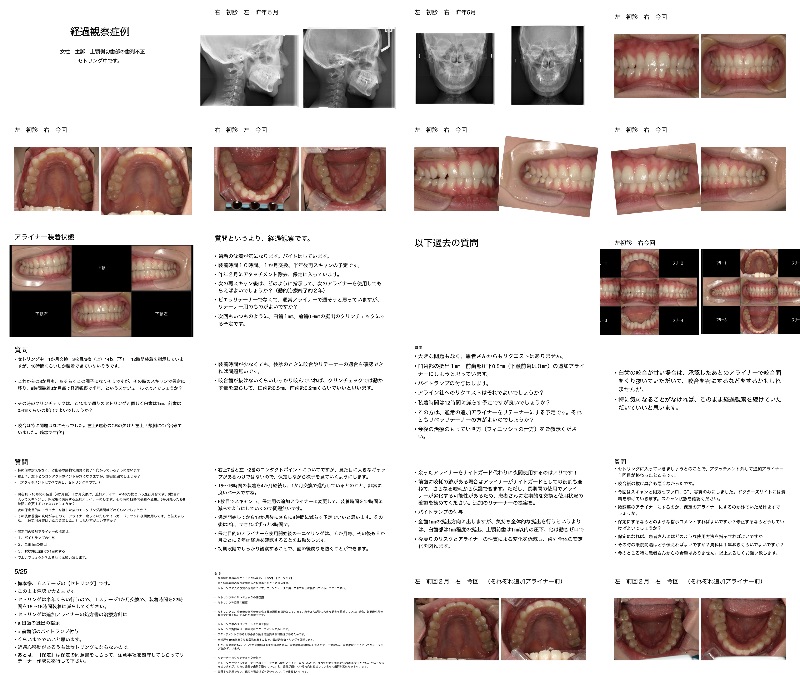

- Q分析治療計画

K君、WEBセフにパノラマとCTのスライスあります。左上5が埋伏しており通常どのように矯正するのでしょうか。こちらではこれを出すのは難しいです。あと、右下4の回転と右上5のスペースがなさそうです。

よろしくお願いいたします。 - A正規会員もしくはQAアクセス会員になると、Aが表示されます。